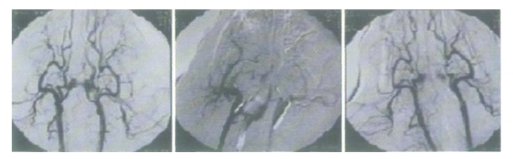

动脉结扎模型是最常用的脑缺血制作模型。随着介入技术的发展,采用介入法经导管把猪自身的血制成新鲜的血栓或者气囊阻断小型猪双侧咽升动脉建立脑缺血模型。具体造模方法如下:经股动脉穿刺插入导管,沿导管插入2个冠脉球囊到达左右咽升动脉,打开球囊堵塞双侧咽升动脉阻断大脑供血。堵塞45min后撤出球囊,行在灌注术。

DSA介入堵塞小型猪双侧咽升动脉前(左)、阻断期(中)、再通0.5h(右)